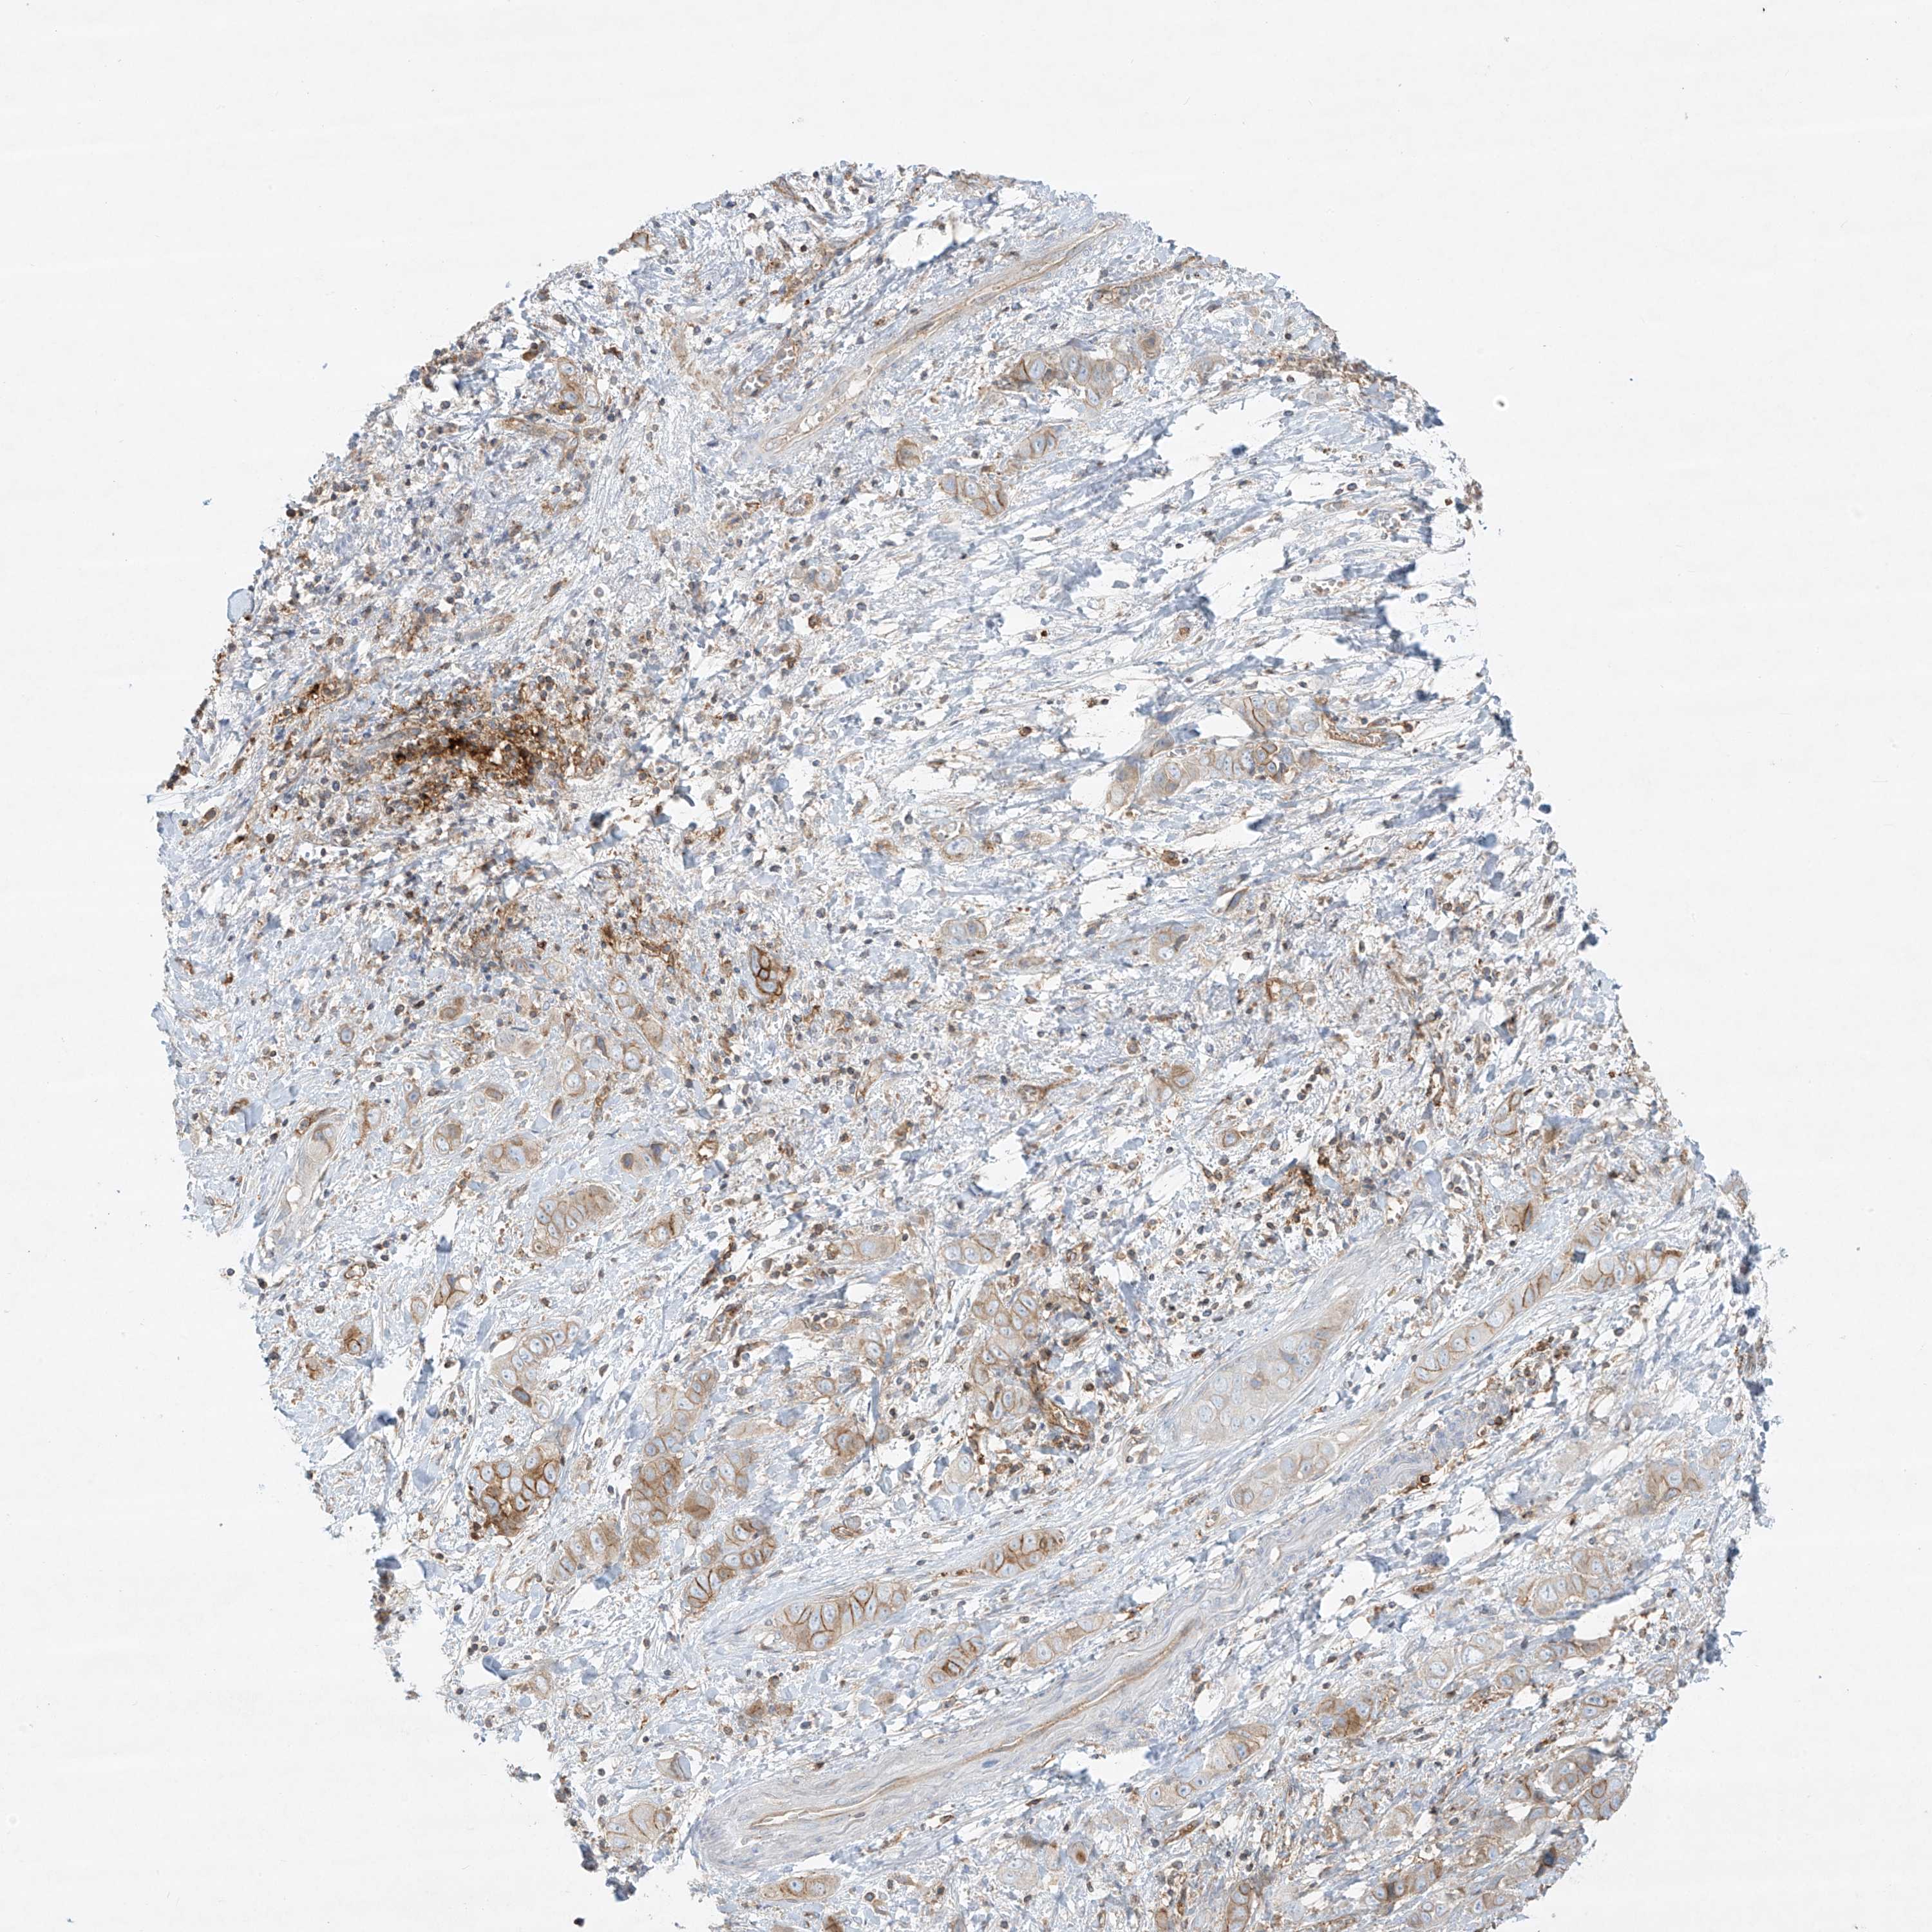

LIVER CANCER - Protein expressioni

A mouse-over function shows sample information and annotation data. Click on an image to view it in a full screen mode. Samples can be filtered based on level of antibody staining by selecting one or several of the following categories: high, medium, low and not detected. The assay and annotation is described here.

Note that samples used for immunohistochemistry by the Human Protein Atlas do not correspond to samples in the TCGA dataset.

Antibody stainingi

Antibody staining in the annotated cell types in the current human tissue is reported as not detected, low, medium, or high, based on conventional immunohistochemistry profiling in selected tissues. This score is based on the combination of the staining intensity and fraction of stained cells.

Each image is clickable and will lead to virtual microscopy that enables deeper exploration of all samples and also displays staining intensity scores, fraction scores and subcellular localization as well as patient and tissue information for each sample.

Antibody HPA031454

Antibody CAB024589

Cholangiocarcinoma

Carcinoma, Hepatocellular, NOS